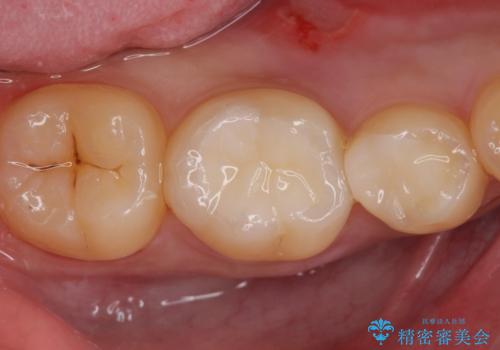

古い樹脂を除去してe-maxインレー

拡大鏡下で古い樹脂を除去し、虫歯がない事を確認してe-maxインレーで治療を行いました。

適合の良い詰め物が入りました。

セラミックは虫歯の再発のリスクが少ないです。